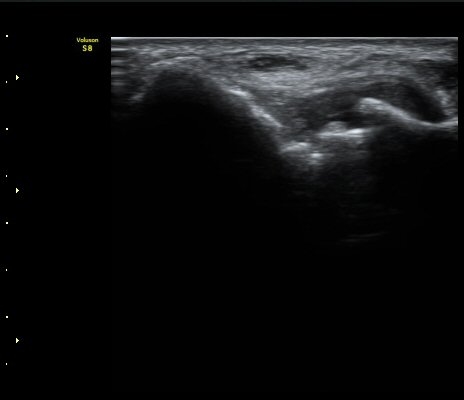

ÃÊÀ½ÆÄ °Ë»ç